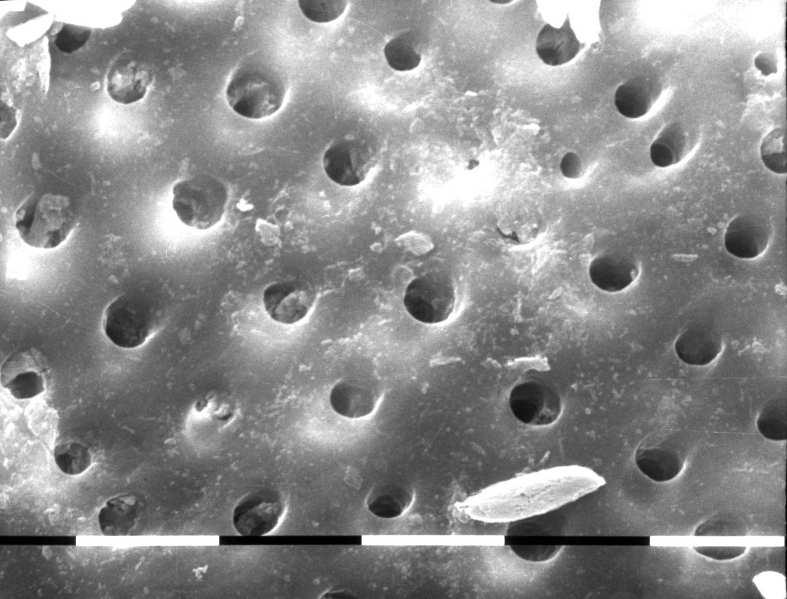

Fig.5 G1 representative sample image at medium third. 810nm diode laser irradiation at 2,5W pulsed mode, 10ms 50%on/off, in EDTA wet canal - 5sec three times: the root canal surfaces are cleaned and exhibit opened dentinal tubules, some residual debris and smear layer still present. No evidence of thermal damage.